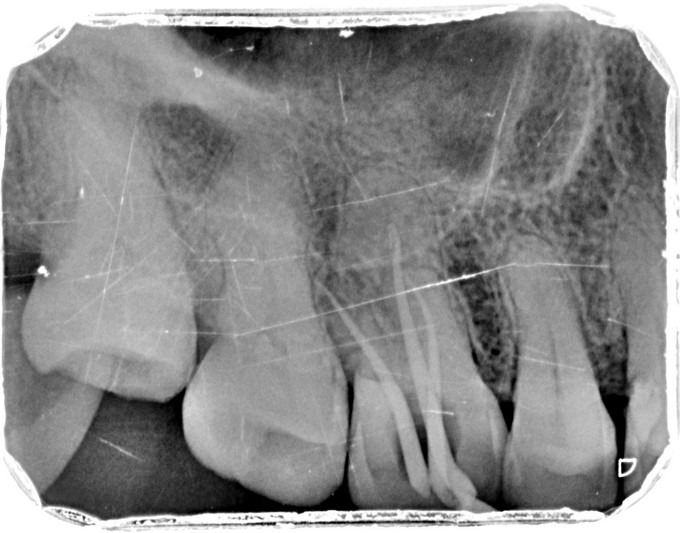

临床检查:16牙合面充填物完好,探疼(+),冷(++),叩(-),松动度(-),无窦道,牙周正常. 辅助检查:X线示16龋坏累积髓腔,根尖周牙周膜略增宽。

诊断:16继发龋伴牙髓炎 治疗:经患者知情同意后,16局麻去除原有充填物降牙合,开髓拔髓寻找根管口,建立直线通路,扩通根管,确定工作长度。S3/EDTA凝胶镍钛器械,低浓度次氯酸钠冲洗根管,预备至35/04,氢氧化钙诊间封药,一周后复诊,试主尖X线示恰充,试干根管,导AH-PLUS糊剂,VDW热压胶垂直加压根充,术后见根管恰充,暂封观察嵌体修复。